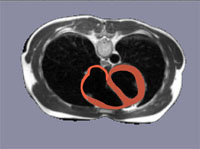

Schnittbild

Zur Orientierung im Volumen besteht die Möglichkeit, eine beliebig orientierte Schnittebene durch den Oberkörper in einem Kernspintomographiedatensatz einzublenden, welcher die Grundlage des verwendeten Herzmodells ist.